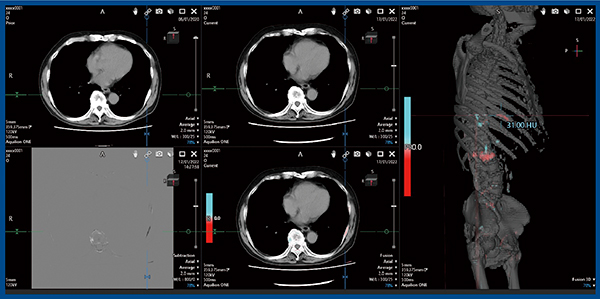

症例2は,80歳代,男性の前立腺がんで,ホルモン療法中である。3Dフュージョン画像では,L1の圧迫骨折に目が行くが,左仙骨にも転移が見られ,さらに左第8肋骨にも溶骨性変化が認められ,新たな転移が生じていることがわかる(図3)。通常のCTでは気づくのが困難な病変であるが,Bone Subtractionにより検出することができた。

図3 症例2:80歳代,男性,前立腺がん